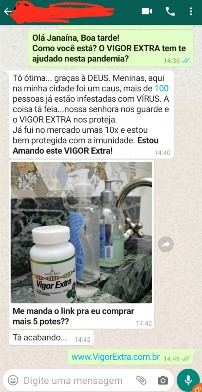

Hoje o VIGOR EXTRA é o melhor e mais completo multivitamínico do mercado!

Aumente a sua Imunidade e tenha mais Energia e Disposição com o VIGOR EXTRA!

O resultado é uma vida mais tranquila e cheia de saúde para você e sua família, pois ele te protege das doenças sazonais e auxilia o corpo a reagir melhor aos danos do estresse, gripes e resfriados.

De jeito nenhum! Pois não existe vacina contra o

CORONAVÍRUS. Se alguém te prometer isso está

mentindo!

Nossa empresa sempre preza a verdade é

transparência.

O VIGOR EXTRA veio para

ajudar a

aumentar o sistema imunológico com este complexo de

Vitaminas e Minerais, pois assim com o seu corpo

forte e

saudável, você terá grande chance do seu próprio

corpo,

de uma forma Natural, combater o CORONAVÍRUS.